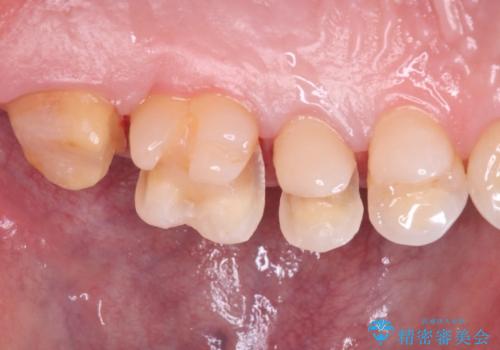

【メタルフリー】銀歯を綺麗な白い歯に

- 銀歯の入っている部分にフロスが引っかかるため、銀歯を適合の良い白いセラミックインレーにやりかえることを提案させていただきました。

一番奥の歯は銀歯に覆われている範囲が多いため、強度などを踏まえ被せ物にしました。

その他2本は詰め物です。

銀歯が綺麗な白い歯になりました。

適合がとてもよいので、フロスの引っかかりも解消されました。